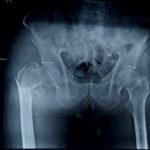

Trauma surgery involves the treatment of fractures and injuries caused by accidents, falls, or high-impact injuries. These injuries may affect bones, joints, and surrounding soft tissues, and often require timely surgical intervention to restore alignment, stability, and function.

Complex trauma surgery is required for severe injuries such as multiple fractures, joint injuries, open fractures, or injuries involving previous implants or deformities. These cases need advanced surgical techniques, careful planning, and specialized orthopedic expertise. The aim of trauma and complex trauma surgery is to promote proper healing, restore movement, and help patients return to daily activities safely.